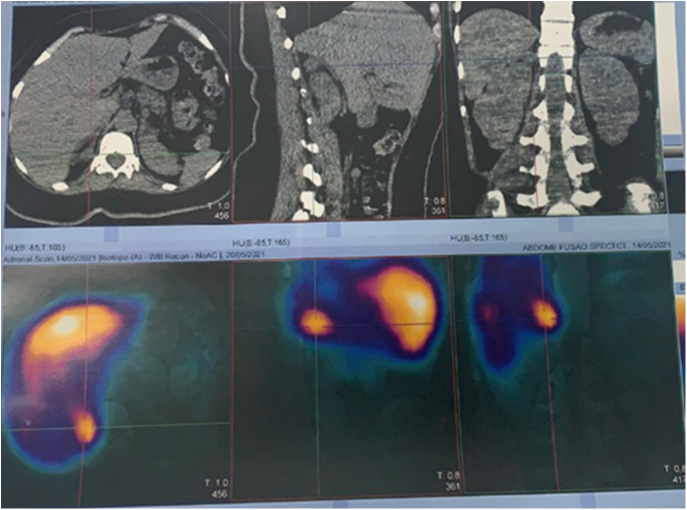

Summary: The case report outlines a 33-year-old woman with neurofibromatosis type 1 (NF1) presenting complex symptomatology including a cervical mass, bone pain and significantly elevated calcium and parathyroid hormone levels, indicative of parathyroid carcinoma accompanied by cystic fibrous osteitis. Intriguingly, an incidental finding of an adrenal nodule prompted investigation, leading to the diagnosis of pheochromocytoma. Surgical intervention confirmed the presence of pheochromocytoma and parathyroid carcinoma. Genetic analysis corroborated NF1 with a pathogenic variant in the NF1 gene. The patient's clinical manifestations, coupled with the presence of café-au-lait spots and axillary freckles, supported the diagnosis of NF1. This case not only highlights the challenging diagnostic landscape of NF1 but also underscores the rarity of the co-occurrence of parathyroid carcinoma and pheochromocytoma within the context of NF1. It emphasizes the necessity for heightened clinical suspicion and comprehensive evaluation in patients with NF1, particularly in those presenting with endocrine abnormalities. Further investigation into the underlying mechanisms linking these conditions is warranted to elucidate their pathophysiological interplay and inform optimal therapeutic strategies for affected individuals. This case underscores the importance of multidisciplinary collaboration in the management of complex NF1-associated manifestations, with an emphasis on early detection and tailored intervention to optimize patient outcomes.